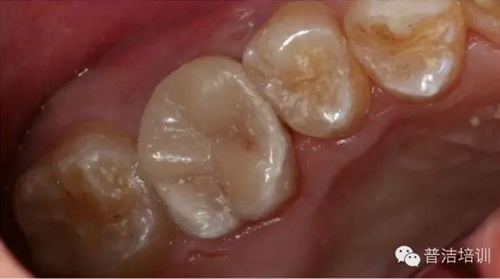

部分病例:

改變了什么?